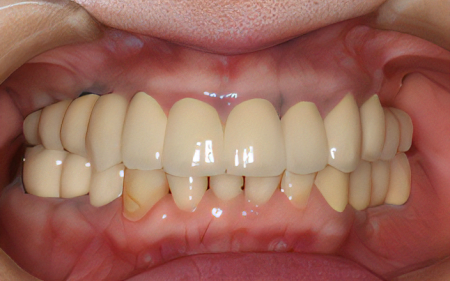

2024.08.1750代女性「前歯がぐらぐらして痛みがある」ブリッジとインプラントで揺れることなくお口全体で物を噛めるようになった症例